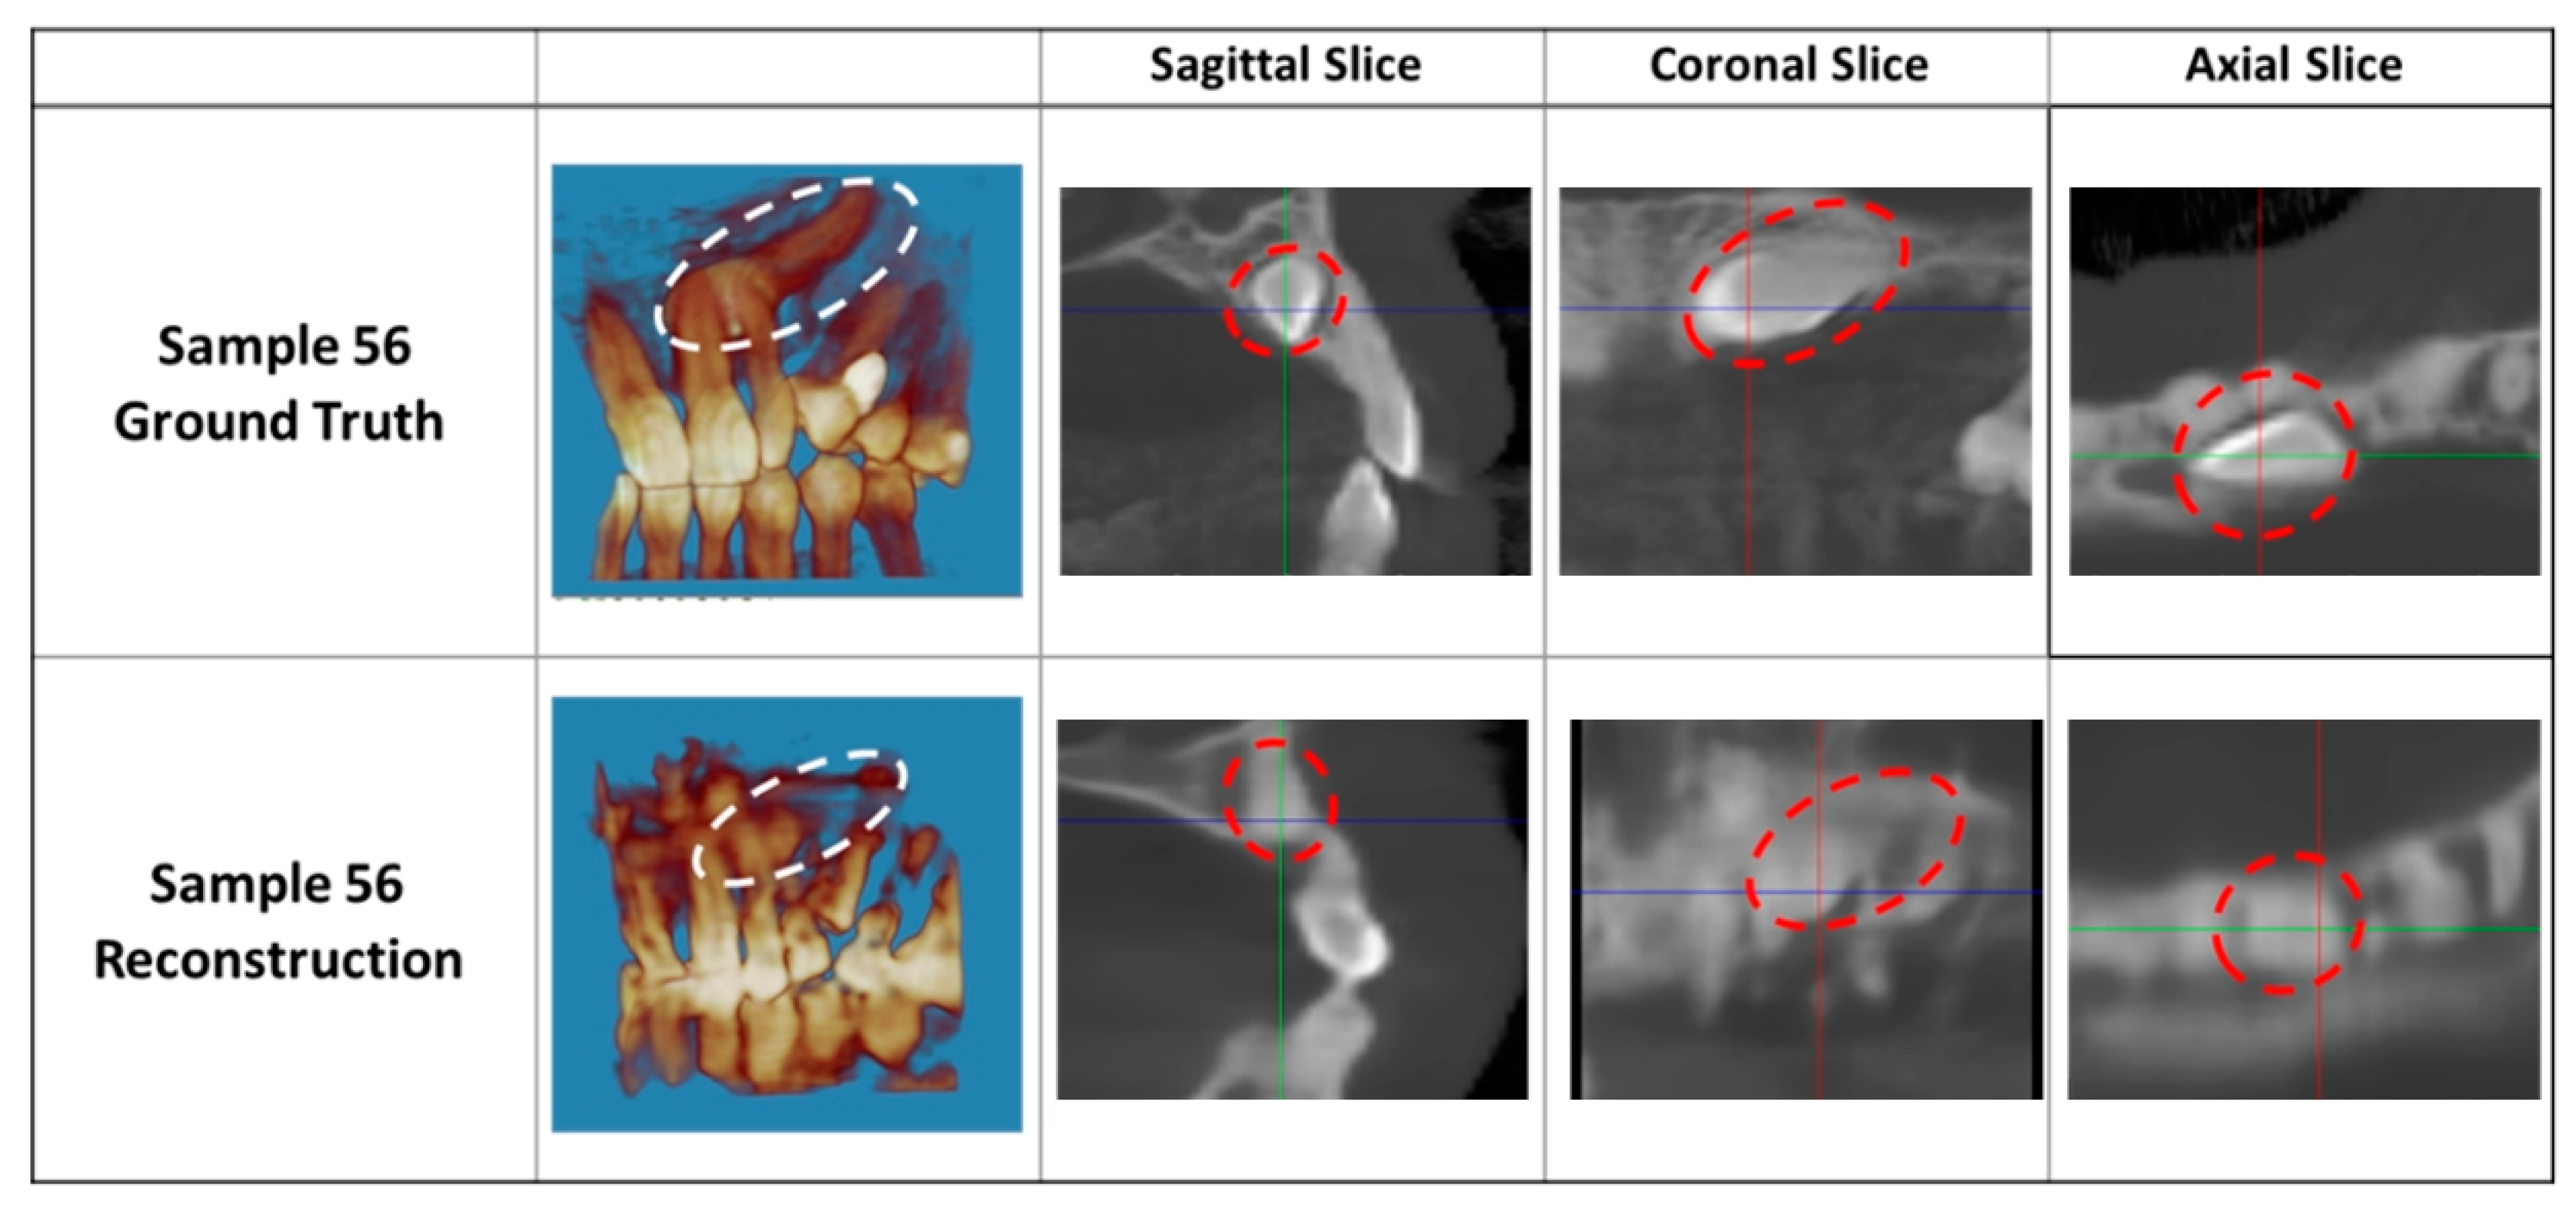

3. Results